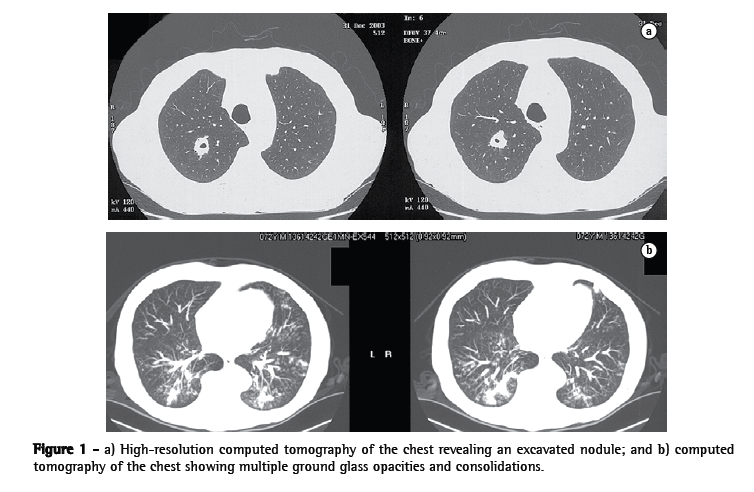

A 71-year-old man, recently diagnosed with Cushing's syndrome due to an adrenal tumor, complained of cough, dyspnea and fever. Physical examination showed that oxygen saturation on room air was 88%. Laboratory tests revealed anemia, thrombocytopenia and elevated levels of hepatic aminotransferase, as well as cholestasis, hypertriglyceridemia and an extremely high serum ferritin level (10,580 μg/L; normal range, 20-250 μg/L). Normal magnetic resonance cholangiopancreatography and ultrasonography ruled out obstruction of the biliary system. To investigate the anemia, bone marrow aspiration was performed, and the results were consistent with a diagnosis of MAS. The aspiration culture results were negative. A chest CT scan revealed an excavated nodule, together with ground glass opacities and consolidations (Figure 1). Bronchoscopy was then performed. Cultures of the bronchoalveolar lavage fluid were negative, and a transbronchial biopsy of the right lower lobe showed that hemosiderin-laden macrophages were abundant in the alveolar spaces, and that there was no significant pleomorphism or mitotic activity. There was lymphocytic infiltrate in the alveolar septa, which presented thickening. These histopathological findings are also consistent with MAS. Considering this diagnosis, intravenous pulse human immunoglobulin was initiated (1 g/kg daily for 2 days).(1) After 20 days, the anemia, hepatic alterations, pulmonary infiltrates and hypoxemia disappeared, and the serum ferritin level normalized. Three years after the immunoglobulin therapy, the patient presented normal chest CT findings and laboratory test results, reporting no complaints.

This was the first reported case of MAS in which the combination of excavated nodule, ground glass opacities and pulmonary consolidations was observed on an HRCT scan (Figure 1). This finding is important because it includes MAS in the differential tomographic diagnosis of pneumonia, lymphoma, pulmonary vasculitis, alveolar hemorrhage, tuberculosis, nocardiosis and fungal disease.(5-9)